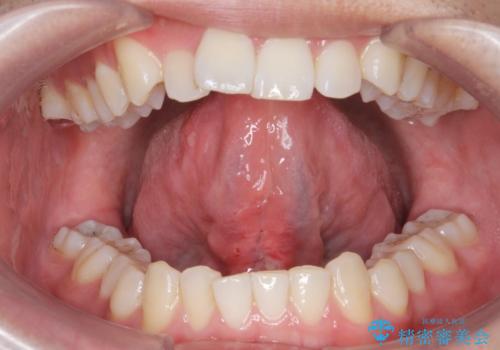

[ 舌小帯の形成術 ] ラ行の発音を改善したい

![[ 舌小帯の形成術 ] ラ行の発音を改善したいの症例 治療前](https://seimitsushinbi.jp/wp/wp-content/uploads/2024/08/acee470463c1189e4b61545af4154c68-500x350.jpg?v=1723775372)

![[ 舌小帯の形成術 ] ラ行の発音を改善したいの症例 治療後](https://seimitsushinbi.jp/wp/wp-content/uploads/2024/08/d2ed5db8e0b29e9cd54a7a382972d064-500x350.jpg?v=1723775393)